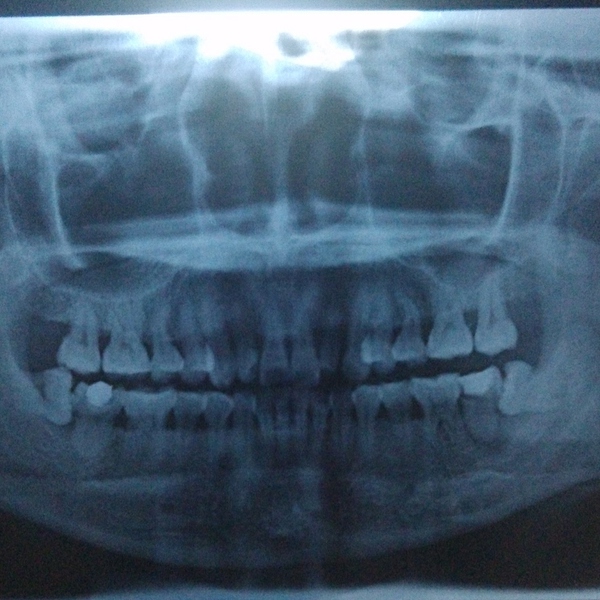

牙齿萌出困难称为"阻生齿"或"埋伏牙"。阻生齿最常见于下颌第三磨牙,俗称智齿,此牙萌出年龄在18岁前后,由于萌出前其它牙齿都早已站好队列了,等智齿生长出来时,就会受到其它牙齿的排挤,故而萌出困难,形成了阻生齿或埋伏牙,我们称之为"阻生智齿"。

阻生智齿会产生很大危害。

(1)冠周炎:智齿因阻生而使牙冠不能完全外露,牙冠周围的牙龈成袋状,极易积存食物、滋养细菌。当全身抵抗力下降时引起急性冠周炎。

(2)间隙感染:冠周炎的炎症可能进一步向肌肉间隙内扩散造成间隙感染。

(3)第二磨牙龋坏:向前倾斜的阻生智齿,因经常在邻牙间积存食物,易发生邻牙(下颌第二磨牙)龋坏。

(4)其它:阻生智齿还可能形成牙源性颌骨囊肿、骨髓炎、颞颌关节病等。